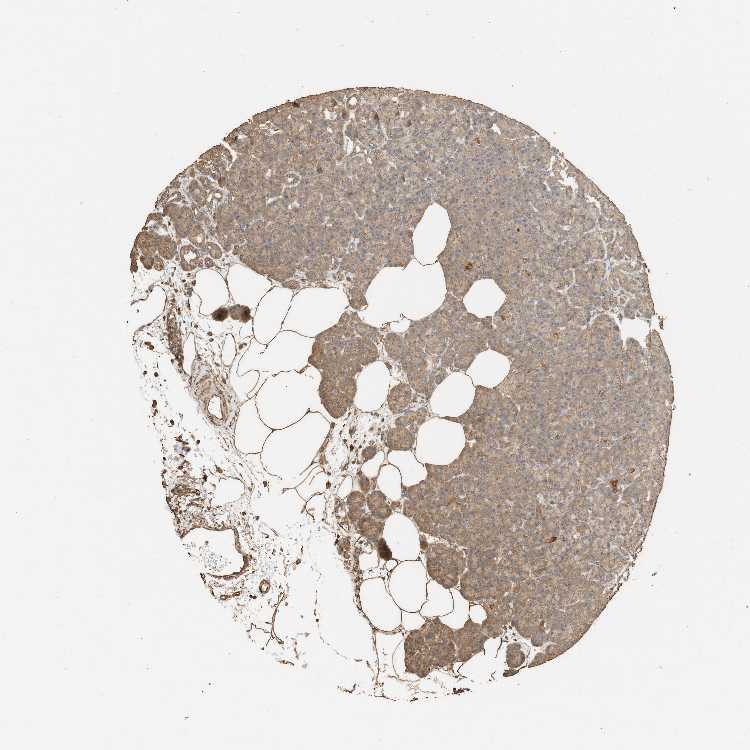

PANCREAS - Antibody stainingi

Antibody staining in the annotated cell types in the current human tissue is reported as not detected, low, medium, or high, based on conventional immunohistochemistry profiling in selected tissues. This score is based on the combination of the staining intensity and fraction of stained cells.

Each image is clickable and will lead to virtual microscopy that enables deeper exploration of all samples and also displays staining intensity scores, fraction scores and subcellular localization as well as patient and tissue information for each sample.

Antibody HPA022948Antibody HPA022962

Exocrine glandular cells LowNot detected

Pancreatic endocrine cells MediumLow